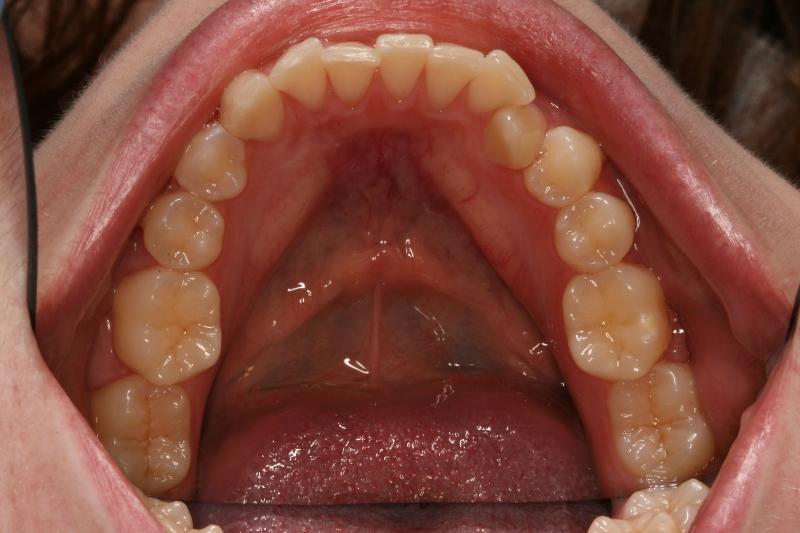

|

The occlusal view of the mandibular arch pictured on the left illustrates a slightly crowded arch. Close examination reveals a supernumerary mandibular central incisor. This is not a common anomaly and illustrates the importance of careful identification and charting in dentistry (courtesy of Dr. BM Cleghorn, Dalhousie University).